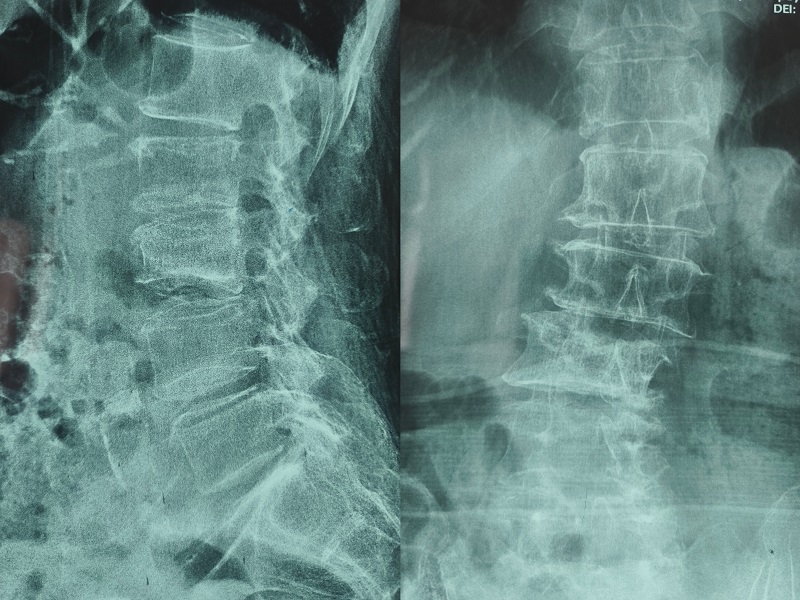

術前診斷:腰椎側彎、陳舊性腰椎壓縮性骨折(L2L3)、重度骨質疏松

術前圖像